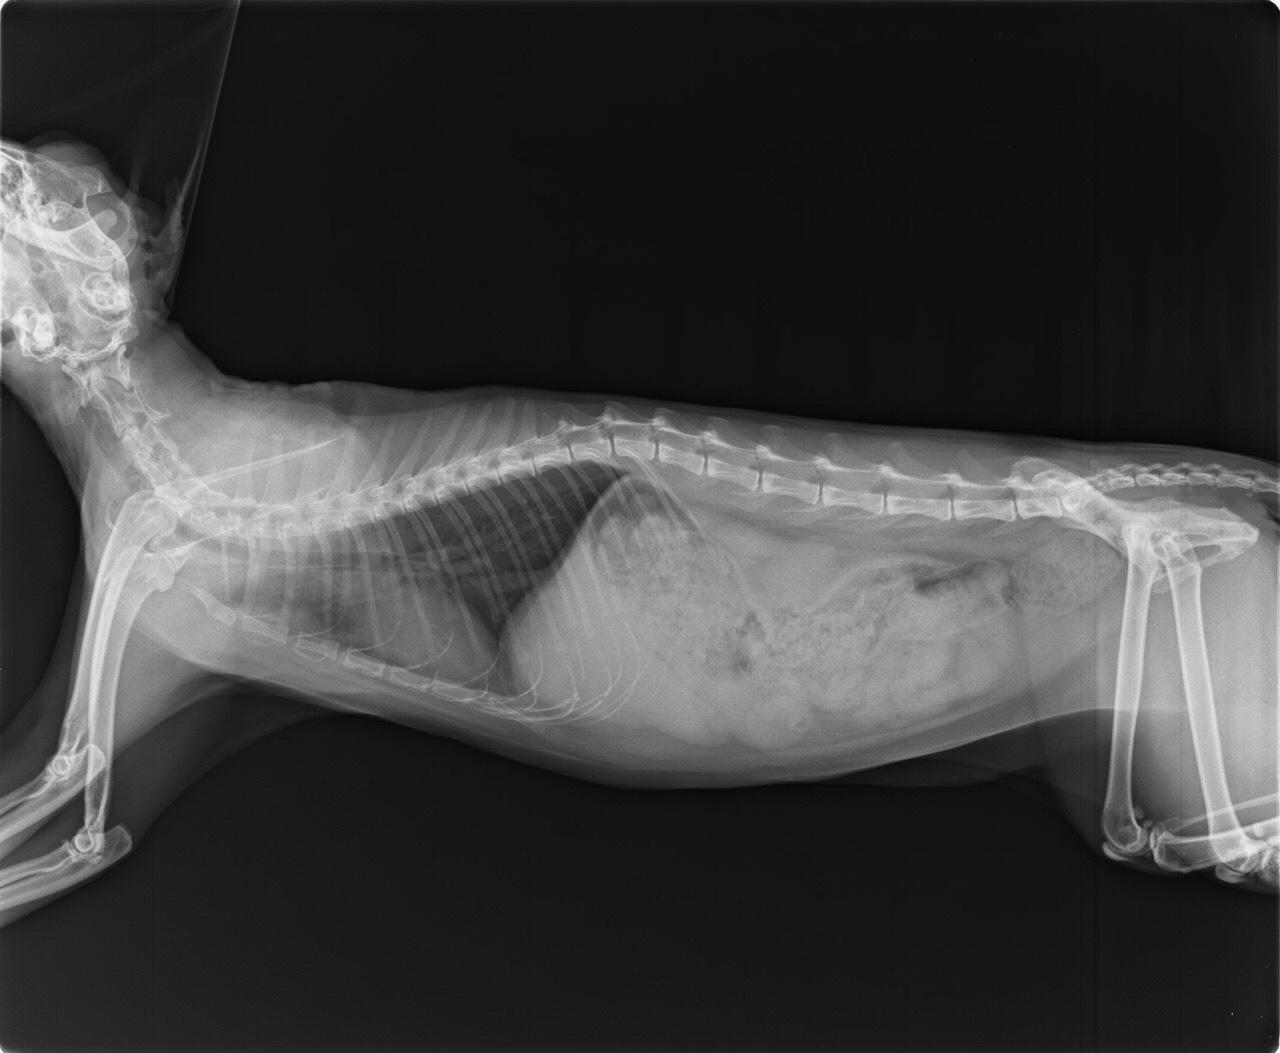

25日醫生說先可讓胖達出院休養,看她在沒有點滴治療下,服用口服藥物的狀況如何,由於胖達貧血又有貓愛滋,加拍X光檢查,看起來體內無明顯異樣,先帶回服藥休息

27日一早趕緊送醫,醫生說應該是消化系統出血,要禁食,留院治療,晚上探視,精神很好,禁食中,吃胃乳治療,有吐些毛球,但沒再吐血了

胖達4/29-5/2持續住院治療,有時會吐,但吐口水或毛雜雜,大便顏色比較深,不過有漸漸好轉,食慾感覺變比較差,吃得比較少些,精神不錯